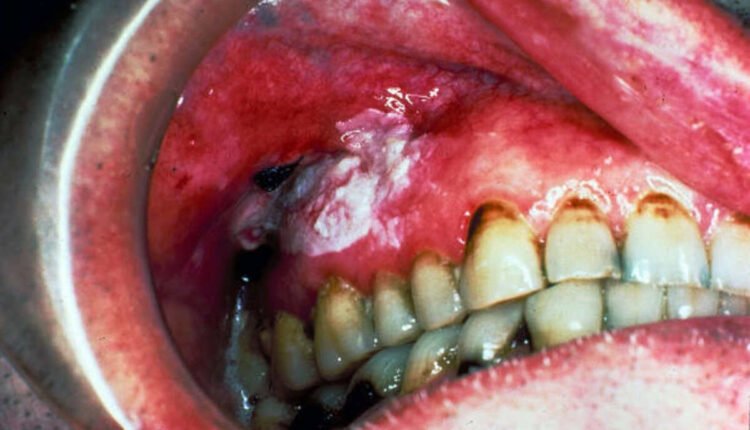

Nonhomogeneous leukoplakia

There are several different types of nonhomogeneous leukoplakia lesions. While the majority of these lesions are benign, some are not. Nonhomogeneous leukoplakias may be nodular, irregularly flat, or erythematous. Verrucous leukoplakia, for example, is an aggressive type of leukoplakia that may progress to cancer.

Nonhomogeneous leukoplakia is a condition in which the oral tissue is primarily white or blends white and red and often takes on an irregular shape. The most common treatment for this lesion is surgery. Surgical resection is the most effective method for removing pathologic tissue, allowing for examining margins and pathology. In addition, surgical resection is less invasive, and there are fewer risks of scarring. Using CO2 laser excision techniques has several advantages over a scalpel, such as reducing intraoperative bleeding and decreasing the need for flaps.